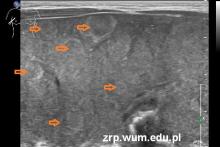

Wątroba znacznie powiększona, w całości o nieprawidłowej strukturze, z bardzo licznymi zmianami ogniskowymi o charakterze meta.

(guz - białe strzałki; nadnercze – czarna strzałka; nerka – czerwona strzałka; meta w wątrobie - kilka zmian oznaczono pomarańczowymi strzałkami).